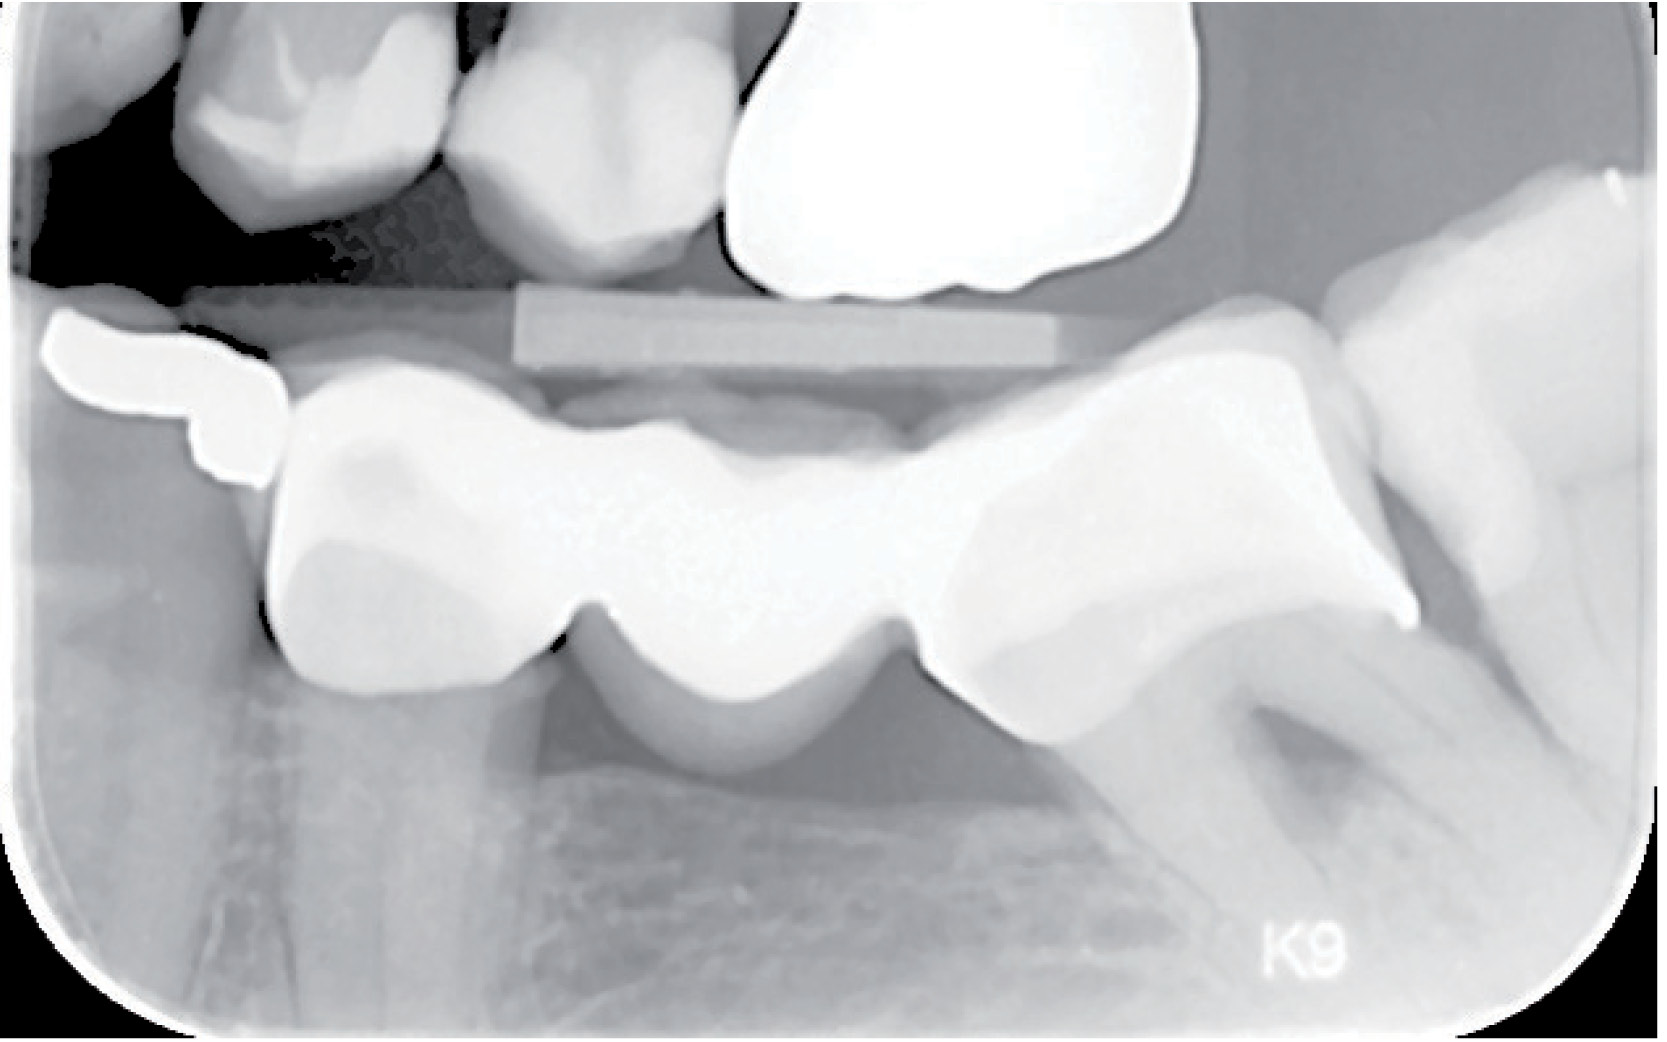

Fig. 1 Bitewing pre-operativt

67 år gammel mannlig pasient. Dyp karies lesjon 37d og 38m. (Fig. 1) 37 behandles med en ny bro siden den gamle var slitt. 38 er et perfekt kasus for å behandle med den nye hybridglassionomeren Equia Forte fra GC, i stedet for en komposittfylling. Dette er begrunnet i den vanskelige posisjonen av kaviteten, hvor det er vanskelig å tørrlegge. Videre har denne pasienten en veldig stor og aktiv tunge, noe som vanskeliggjør behandlingen, og kofferdam går ikke å bruke på pasienten. 37 reneskaveres og det legges Fuji II LC fra GC i de dypeste kavitetene (brukt i henhold til forskriftene og lys herdet). Deretter prepareres det til ny bro. Det tas et konvensjonelt avtrykk og en 3-ledds bro blir fremstilt.